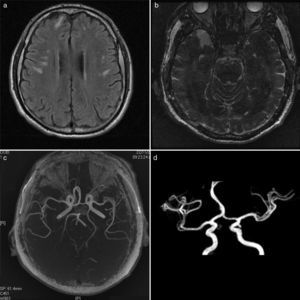

a) IRM en secuencia T1 con imágenes hiperintensas de daño microvascular en sustancia blanca de lóbulos frontales y parietales bilaterales; b) IRM secuencia de inversión recuperación, con lesiones en lóbulo temporal derecho; c) Angiorresonancia magnética mostrando circulación cerebral anterior sin afección de grandes vasos; d) Angiorresonancia con polígono de Willis normal.

Un varón de 54 años consultó por anacusia súbita bilateral, cefalea y vértigo. Contaba con antecedente de pancreatitis aguda con DM secundaria 4 años previos. Hipotiroidismo primario de 7 años. Fue abordado por otoneurología y posterior a la audiometría se concluyó anacusia neurosensorial bilateral y lo manejó con dexametasona transtimpánica. Infectología prescribió ganciclovir 12mg/kg/día durante 10 días+prednisona 50mg/día durante 4 semanas. Los estudios de neuroconducción revelaron potenciales auditivos de latencia corta sin respuesta. La logoaudiometría reportó ausencia de respuesta a intensidades máximas. Se canalizó a terapia de lectura labiofacial y a reumatología por hallazgo de aCL. En reumatología diagnosticamos SAF con base en los anti-ß2GP IgM y aCL a títulos altos, anticoagulante lúpico positivo y TTPa prolongado. Posterior a sus estudios inmunológicos (tabla 1) descartamos presencia de lupus. Adicionalmente, en la IRM observamos imágenes hiperintensas subcorticales en lóbulos frontales y parietales bilaterales con comportamiento vascular y reforzamiento normal, lo que demuestra afección microvascular (fig. 1). Debido a que nunca presentó trombosis de grandes vasos, concluimos que se trataba de un SAF primario en su variedad microangiopática.

Nuestro paciente representa un caso prototipo de MAPS, cuyo diagnóstico se estableció con los títulos de anti-ß2GP IgM, aCL, anticoagulante lúpico, TTPa prolongado y manifestaciones microvasculares. La afección a SNC quedó demostrada por los hallazgos típicos en la IRM de afección microvascular, caracterizados por lesiones de predominio en sustancia blanca debido a la mayor vulnerabilidad a la isquemia de esta zona6. En cuanto a la ASBN, constituye una entidad de presentación excepcional, y no obstante que su asociación con la presencia de aCL está bien establecida, los mecanismos patogénicos permanecen siendo un misterio. Se ha sugerido que los antifosfolípido (aFL) activan el endotelio de la circulación coclear y esta sobre regulación ocasiona microtrombos locales e isquemia en el oído interno7. Con relación a las manifestaciones pancreáticas, al descartarse otras entidades nosológicas, es razonable considerar su relación con el MAPS. En este sentido, el primer caso de compromiso pancreático en SAF fue descrito por Bird et al.8 y desde entonces varios casos han sido publicados. Las autopsias muestran inflamación crónica y trombosis en arterias pancreáticas en ausencia de vasculitis9. Respecto a la presencia de hipotiroidismo, aún existe controversia sobre el significado clínico de los aFL en la enfermedad autoinmune tiroidea, pero la evidencia actual apunta a que la producción de anticuerpos anti-tiroglobulina y anti-microsomales se acompaña con la síntesis de aFL como un epifenómeno10.